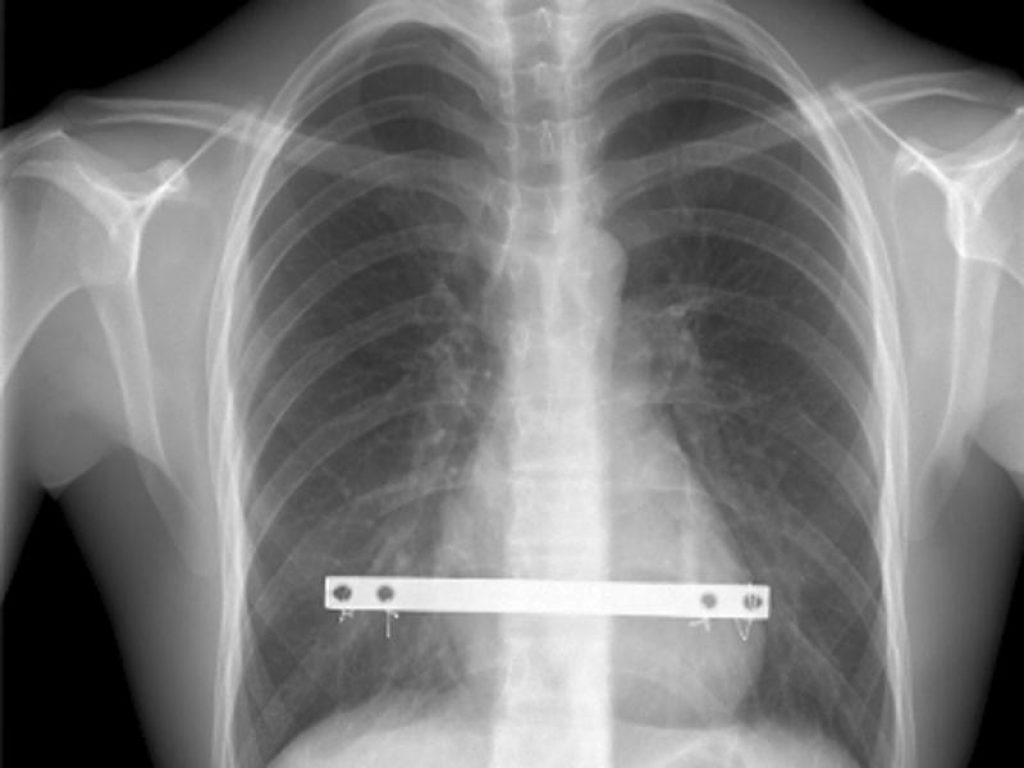

L’opzione più praticata si chiama sternoplastica di Nuss (dal nome del chirurgo che la propose per primo) e permette di correggere la malformazione grazie all’inserimento di un archetto metallico sotto lo sterno. Questa operazione per il pectus excavatum consente di intervenire per via mini-invasiva, attraverso due piccole incisioni ai lati del torace, in maniera video-guidata. Una volta inserito l’archetto, le estremità vengono agganciate alle costole e il centro sposta lo sterno all’infuori, in modo che, sotto questa spinta costante, l’infossatura si raddrizzi. Il candidato ideale per questo tipo di operazione ha 12-16 anni, infatti il supporto metallico deve essere rimosso dopo 3-4 anni, a maturazione ossea completata.